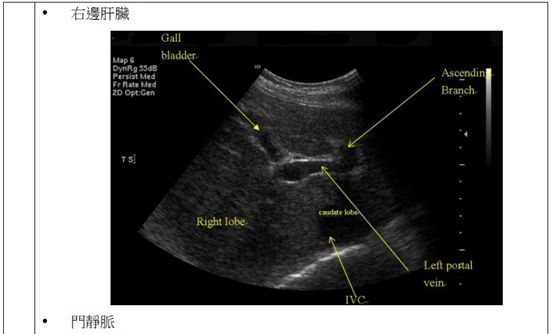

(C)右葉